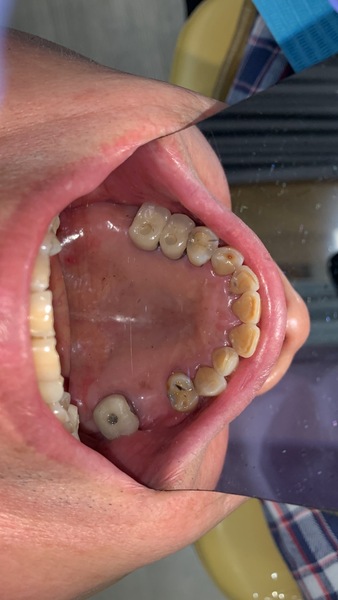

前兩年患者認為自己身體狀況不好,決定牙齒只要壞了,就用活動假牙就可以,不想再花時間和金錢修復牙齒,太累太辛苦了。

奈何牙齒每況愈下,抽了神經後,陸續斷牙,直到累計滿5顆,真的無法再忍耐了。

但患者嘗試過了,覺得活動假牙不好用、很麻煩,且能咀嚼食物有限,因此回頭想要知道有沒有更好的方法可以修復,但不要太長時間的方法。